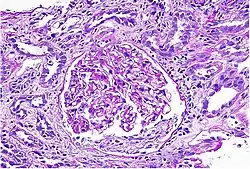

| Acute interstitial nephritis on light microscopy | |

While non-invasive patient evaluation (physical examination, blood and urine testing, imaging studies) can be suggestive, the only way to definitively diagnosis interstitial nephritis is with a tissue diagnosis obtained by kidney biopsy. Pathologic examination will reveal the presence of interstitial edema and inflammatory infiltration with various white blood cells, including neutrophils, eosinophils, and lymphocytes. Generally, blood vessels and glomeruli are not affected. Electron microscopy shows mitochondrial damage in the tubular epithelial cells, vacuoles in the cytoplasm, and enlarged endoplasmic reticulum.[23]